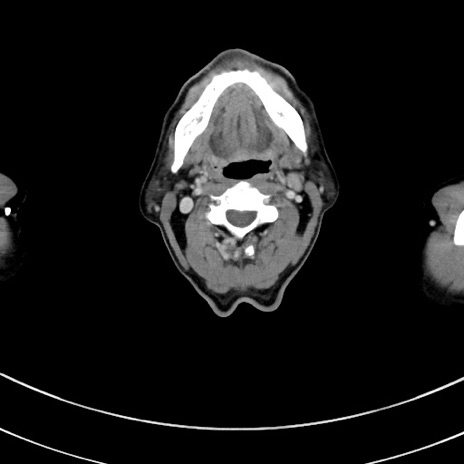

冠状断像